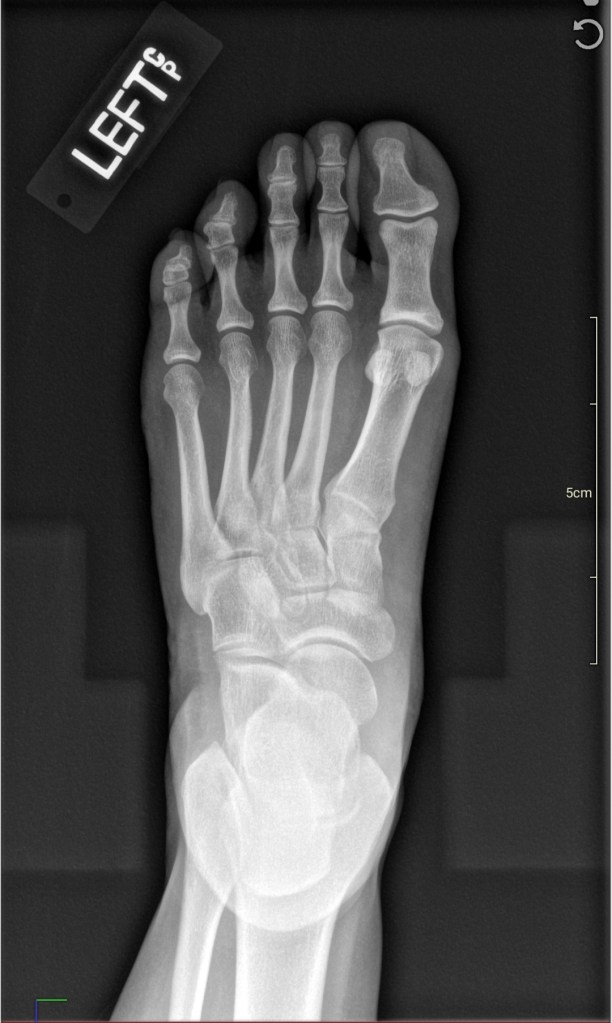

In my follow-up visit a week later with my care team after my neck x-rays, I also mentioned my on-and-off left foot pain.

I get pain in my left heel and in between my third and fourth toe. Sometimes it hurts for days, especially when I’m doing too much on my feet, like dancing.

I’ve had it for years and I have mentioned it to Primary Care once before. I usually forget to bring it up, though, because it usually goes away in a few days and I figured it was normal everyday wear. My doctored ordered x-rays of my left foot and insoles for my shoes.

In those X-rays, we can see a bone spur on my left foot heel – a calcaneal heel spur – that has been causing me pain when I put pressure on my heel. This can stem from Plantar Fasciitis – degeneration of the band of tissue (fascia) at the bottom of your feet that runs from your heel to your toes.

I’ve been given insoles for my shoes and told to only wear sneakers for a few weeks to see if it helps.